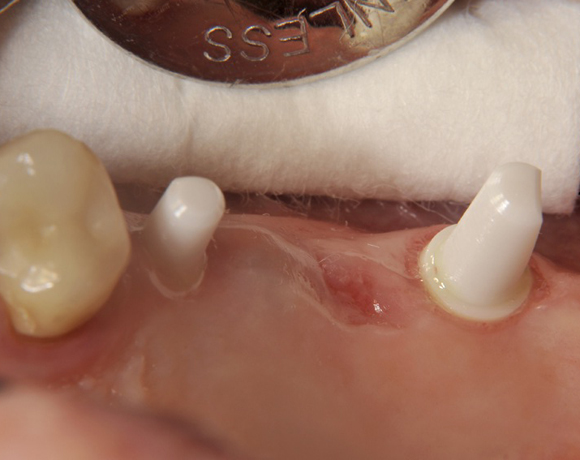

Im vorliegenden Patientenfall wurden für die Zähne 25 und 27 jeweils ein Implantat gesetzt. Nachdem die Implantate eingeheilt waren, wurde 25 – 27 mit einer Brücke versorgt.

Der operative Teil